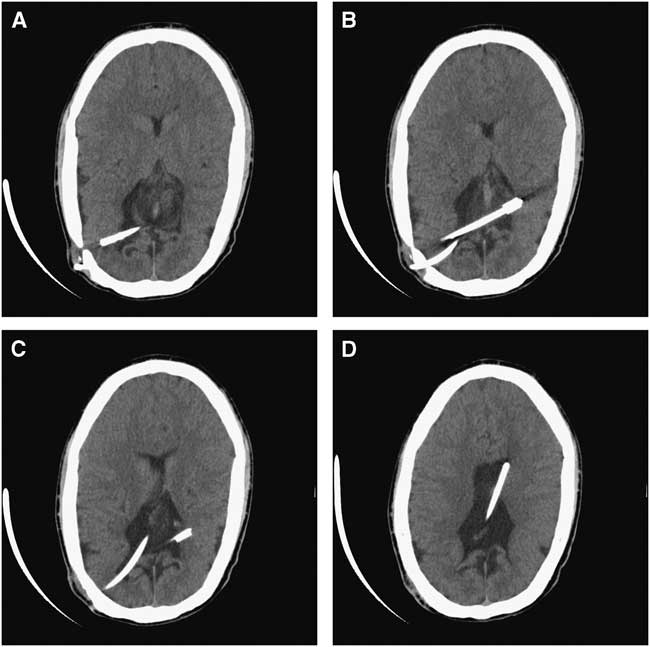

The first patient has cerebral palsy, autism, and congenital hydrocephalus treated with a ventriculoperitoneal (VP) shunt in infancy. At 15 years of age, he presented with increasing lethargy and decreased oral intake. On imaging, a fracture in the proximal portion of his VP shunt was identified, along with increased ventricle dimensions when compared with a prior baseline scan. The shunt system, which consisted of a flanged ventricular catheter, a burr hole valve, and peritoneal catheter, was revised. At surgery, the ventricular catheter had retracted from the cortical surface and was left in situ. A completely new VP shunt system was placed. After a period of 39 days, the patient returned with fever, an elevated white blood cell count of 15.6×109/L (reference range 4.0-11.0×109/L), and an elevated C-reactive protein of 166.6 mg/L (reference range 0-5 mg/L). The shunt was tapped and unidentified gram-positive cocci in pairs were seen. CSF culture ultimately grew coagulase-negative staphylococcus. The shunt was externalized and the patient was treated with intravenous antibiotics. After a period of 15 days later, following confirmation of negative CSF cultures, the patient returned to the operating room. In an effort to reduce the risk of re-infection, it was decided to remove all existing shunt components including the retained flanged ventricular catheter that was disconnected and retracted from the cortical surface (Figures 1A-1D). The flanged catheter was removed endoscopically.

Figure 1 Patient 1. (A-D) Axial CT scan images of the brain demonstrating a retained finned ventricular catheter (Integra LifeSciences Corporation) that has retracted from the cortical surface.